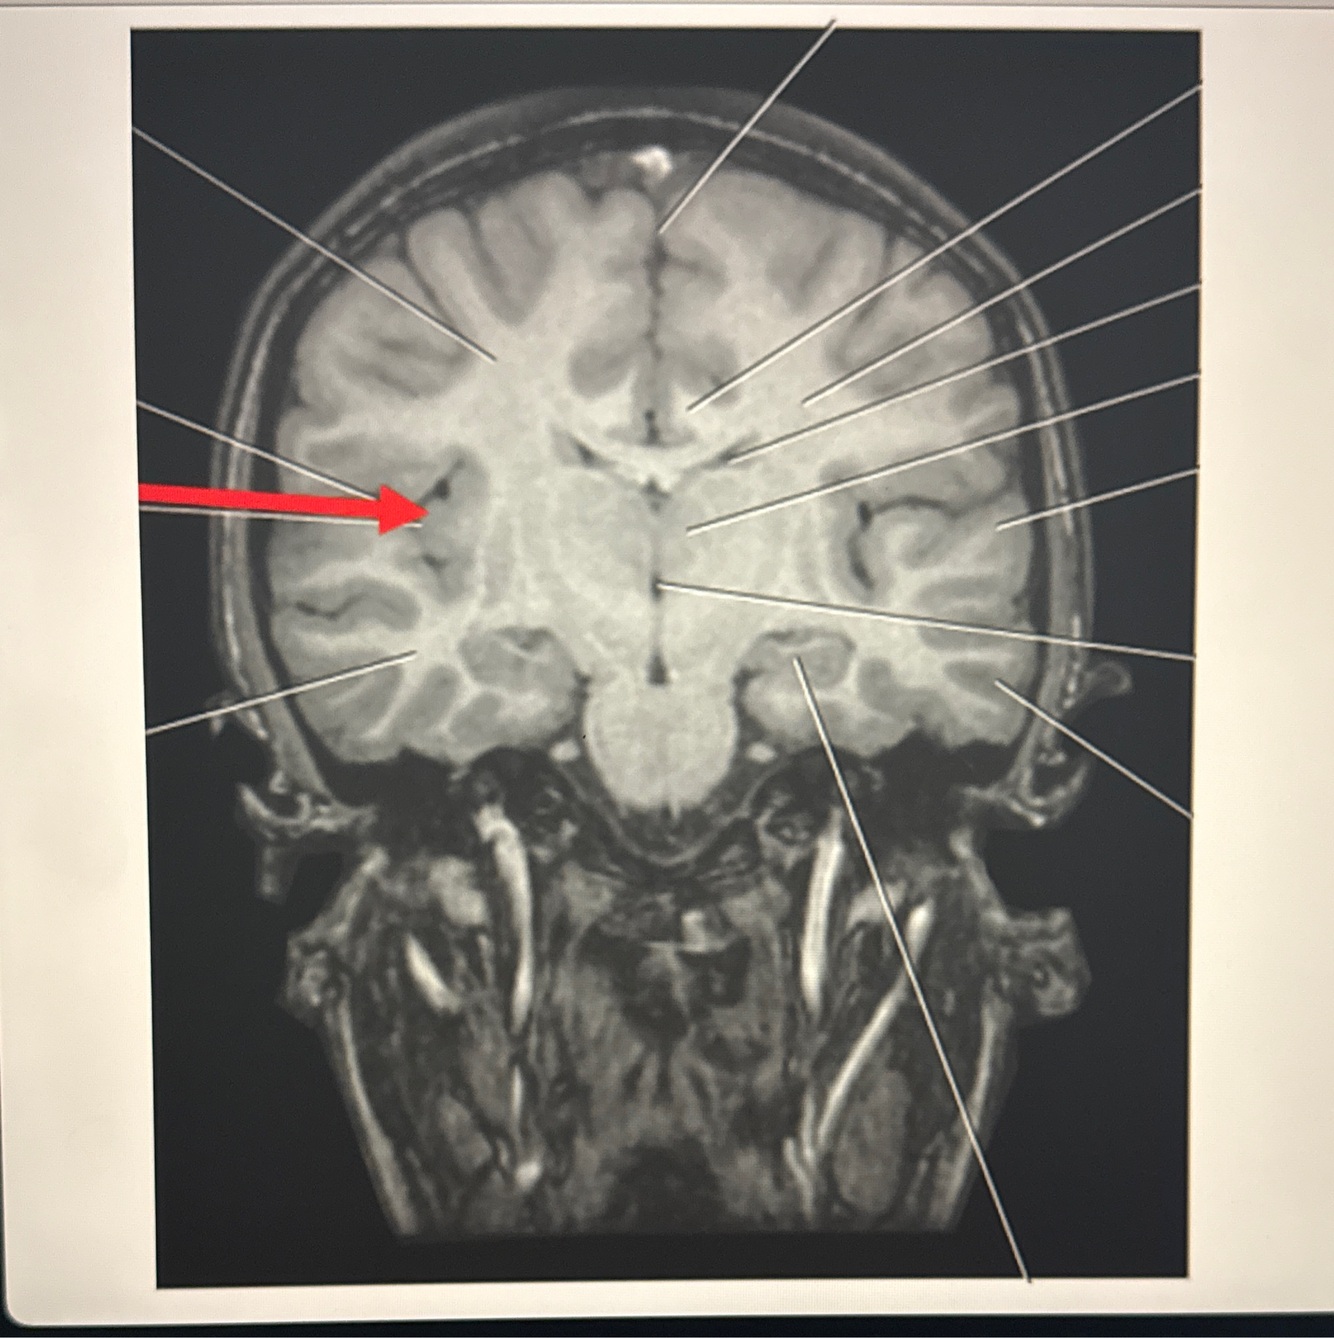

Q

A. Lateral ventricle

B. Insula

C. Cingulate gyrus

D.Parahippocampal gyrus

A